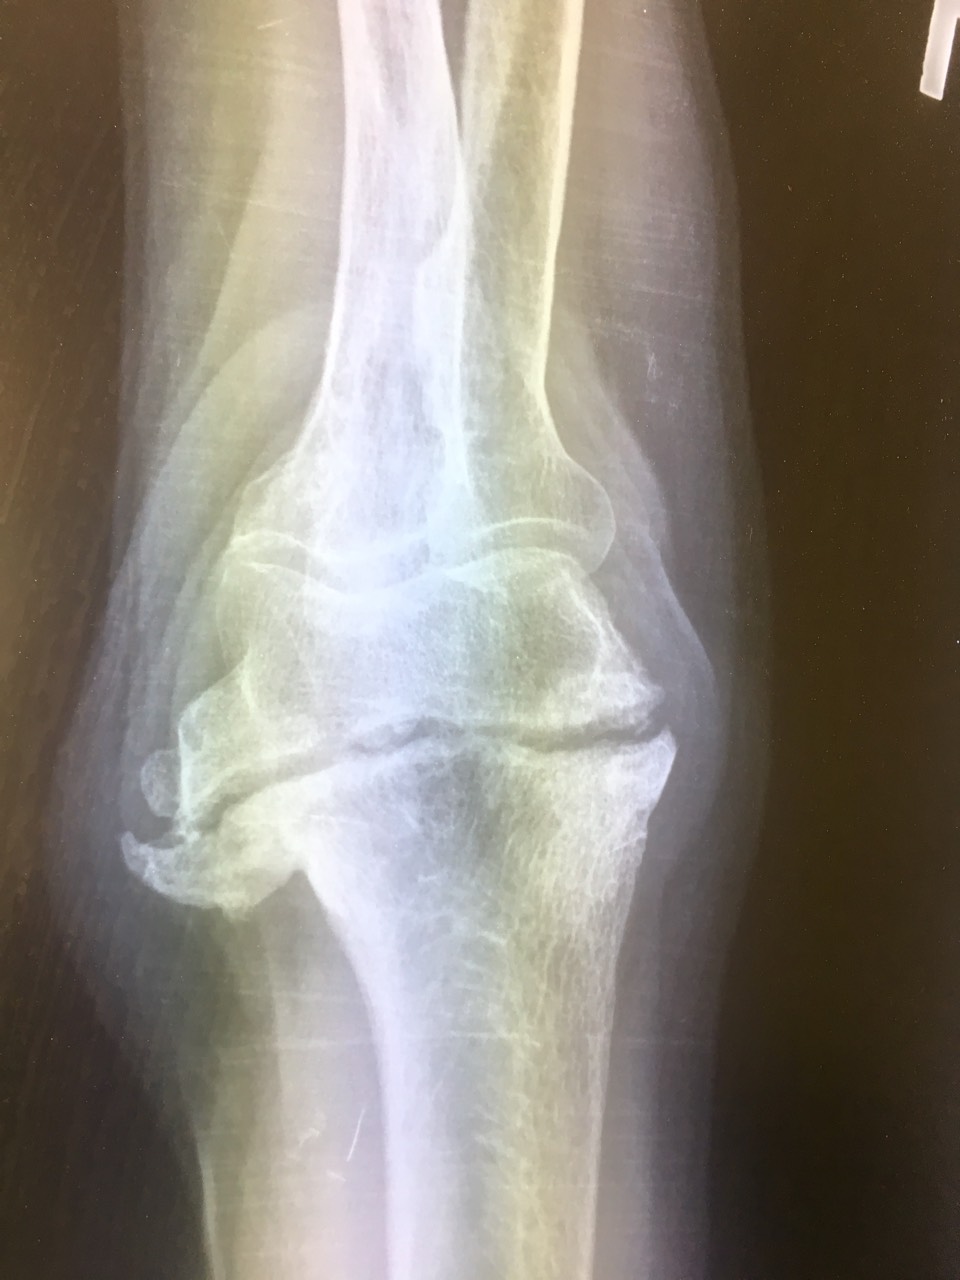

Локтевой перелом форум

Локтевой перелом форум 115 фото